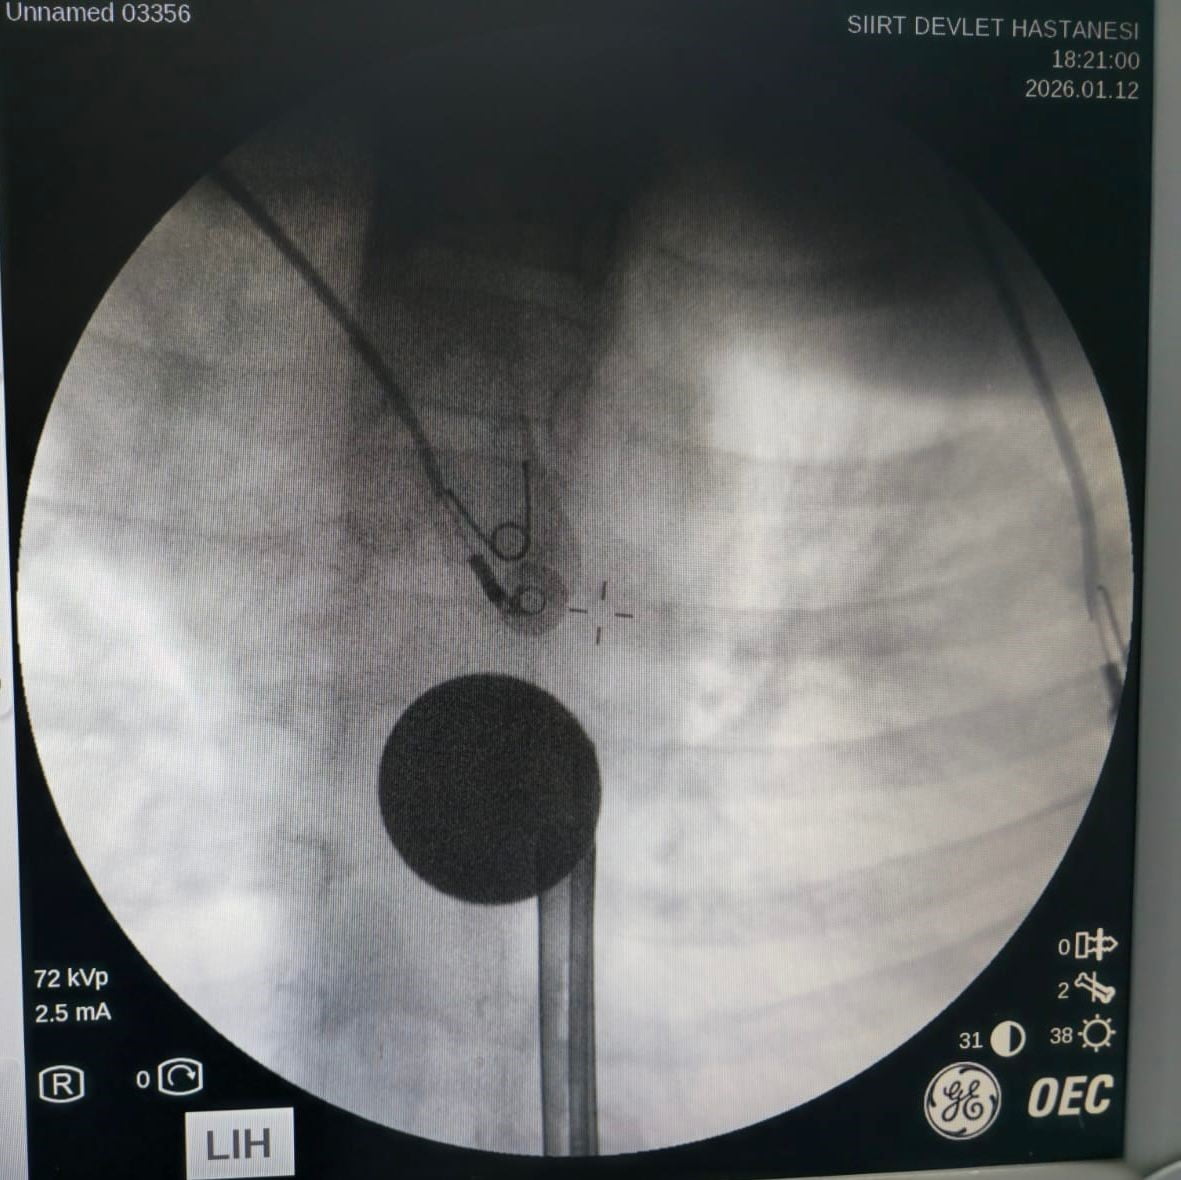

Siirt Eğitim ve Araştırma Hastanesi'ne ailesi tarafından getirilen 8 yaşındaki Y.K., yabancı cisim yutma şikayetiyle acil serviste değerlendirildi. Yapılan görüntüleme ve ilk incelemeler sonucunda madeni paranın yemek borasına kadar ilerlediği tespit edildi.

Gastroenteroloji uzmanı Dr. Yaren Dirik ve kulak burun boğaz hekimi Yasin Gökçınar tarafından ortaklaşa yapılan müdahalede, boğaza kaçan 5 lira çıkarıldı. Operasyonun ardından çocuk bir süre gözlem altında tutuldu ve tedavisi tamamlandıktan sonra taburcu edildi.

Siirt Eğitim ve Araştırma Hastanesi Başhekim Yardımcısı Uzman Dr. Burak Özkan konuyla ilgili olarak, "Hastanemize başvuran 8 yaşındaki hastamızın yemek borusuna kaçan madeni para, gastroenteroloji ve KBB ekiplerimizin koordineli ve titiz çalışmasıyla herhangi bir komplikasyona yol açmadan başarılı bir şekilde çıkarılmıştır. Operasyon süreci sorunsuz geçmiş olup hastamızın genel durumu iyidir" dedi.